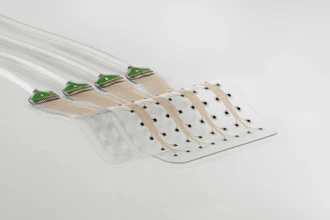

- Component Integration: Integrating multiple components, such as the sensor and the external reader system, requires careful coordination. Injectsense's reader uses both digital and analog systems, which must be compatible regarding power consumption and data transmission. We designed the PCB for the external reader and system, ensuring it could communicate wirelessly with the implanted sensor while maintaining an efficient power profile. We also considered the optimal distance between the sensor and the reader—currently an inch and a half—enabling reliable data transmission from within the eye to an external device. The sensor also incorporates MEMS (Micro-Electromechanical Systems) technology, which allows for precise, low-power, and reliable pressure measurements with a minimal footprint.

- Wireless Data Transmission: For an implantable device to be effective, it must be able to communicate with external systems without requiring cumbersome connections. Injectsense's sensor sends data wirelessly to an external reader, which connects to a mobile application. This data transmission must be both reliable and secure. Promex helped integrate a wireless communication protocol and ensure that the external system could transmit data to the cloud, where healthcare providers will be able to remotely access the information in real time. The device uses Bluetooth Low Energy (BLE) for power-efficient data transmission, ensuring that the patients and doctors can easily monitor IOP without interruption.